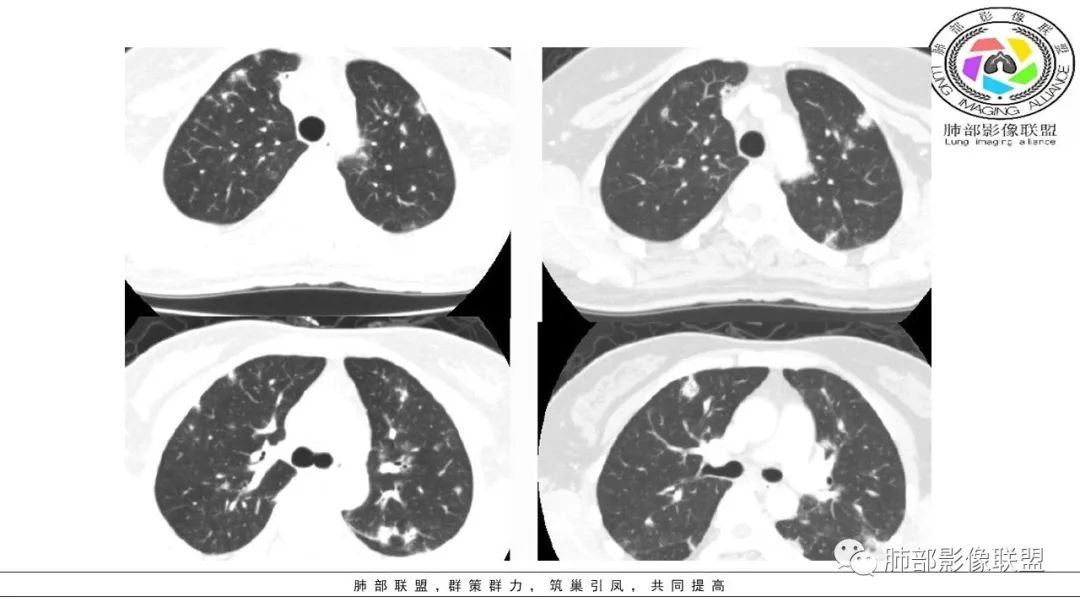

2、病毒一般气道而来,沿支气管进来,与黏膜上皮细胞受体结合并复制,透过粘膜朝周围扩展漫延

3、在过渡区朝外、朝下发展,或者直接进入肺泡腔,沿肺泡壁等间质

4、病毒性肺炎的主战场——小叶核心区域、胸膜下(肺实质区域的间质部分),大气道偶尔受累。 医学百科网 | YxBaike.Com